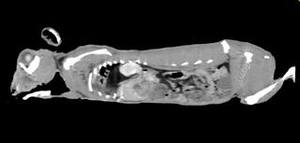

うさぎの横隔膜ヘルニア(CT画像)

エキゾチックアニマルを専門的に診察する動物病院には数少ないヘリカルCTを導入しています。 このヘリカルCTでなければ診断できない外科疾患が診断できることによって様々な手術によって命を救っております。エキゾチックアニマルはもちろん、犬猫でも高度な診断が可能であり、特にさまざまな外科疾患に対応しております。 特に強い分野は3つあります。 ・エキゾチックアニマル ・画像診断(犬猫エキゾチックアニマル) ・外科手術(犬猫エキゾチックアニマル) これらに加えて飼い主さんとの親密なコミュニケーションによって社会貢献させていただいてます。